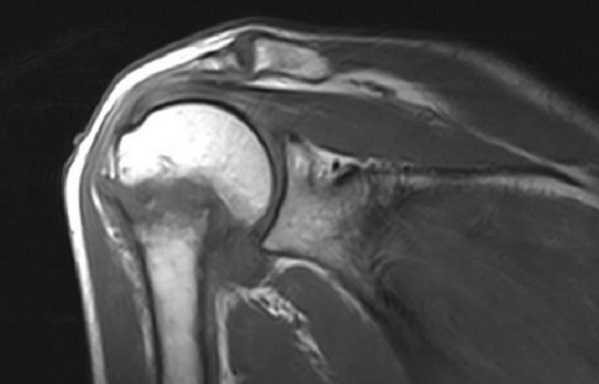

МРТ плечевого сустава в корональной плоскости. Отмечается вколоченный перелом хирургической шейки плечевой кости.